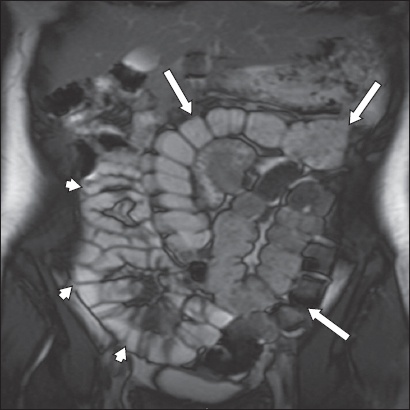

Systemic sclerosis is characterised by widespread collagen deposition in the skin, blood vessels, muscles and internal organs. Up to 50% of cases include small bowel involvement. The classical small bowel follow-through finding is a ‘hide-bound’ appearance of the jejunum and proximal ileum caused by crowding of the valvulae. Hypomotility leads to stasis, bowel dilatation and pseudo-obstruction (

Fig. 12

A 72-year-old woman with systemic sclerosis presented with a two-year history of weight loss and diarrhoea. Coronal true FISP MR enterography image shows gross generalised small bowel dilatation with a paucity of valvulae and no discrete transition point (arrowheads). The findings are typical of pseudo-obstruction associated with systemic sclerosis.